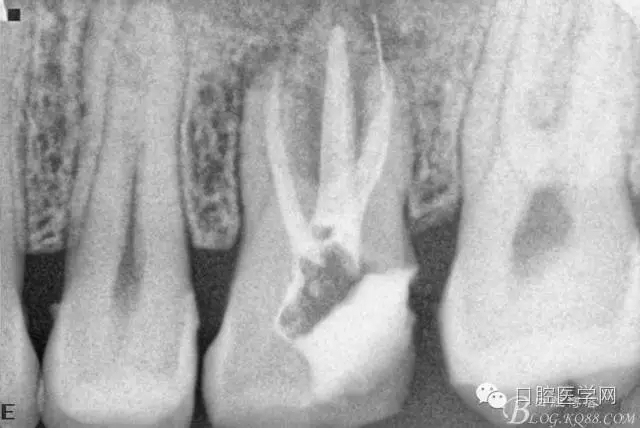

擴根片(可惜遠頰根有一斷針)